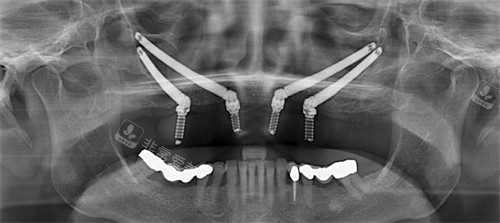

穿颧穿翼种植材料

口腔穿颧穿翼

穿颧穿翼种植牙示意图

穿颧穿翼种植正面图

穿颧穿翼种植分区图解